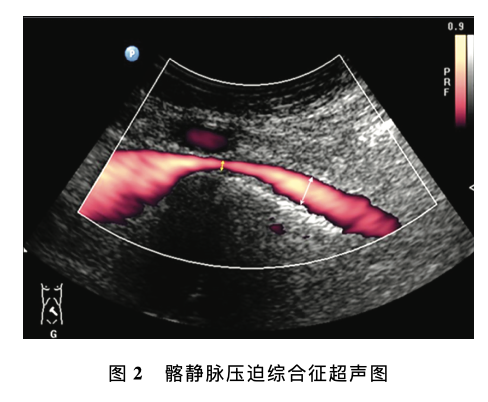

腹部及外周静脉血管超声若干临床常见问题专家共识

发布时间:2023-12-29

意见一:下肢静脉反流超声检查的推荐体位推荐体位为头高脚低位 (建议使用电动检查床), 即检查床头侧高于足侧,与地面夹角约30。条件有限的情况下可选择站立位或坐位,不推荐俯卧位评价下肢静脉反流。意见二:Valsalva (乏氏动作)的适用性乏氏动作主要用于评估隐-股静脉瓣、股静脉近 端静脉瓣的功能,不适于下肢远端静脉反流......